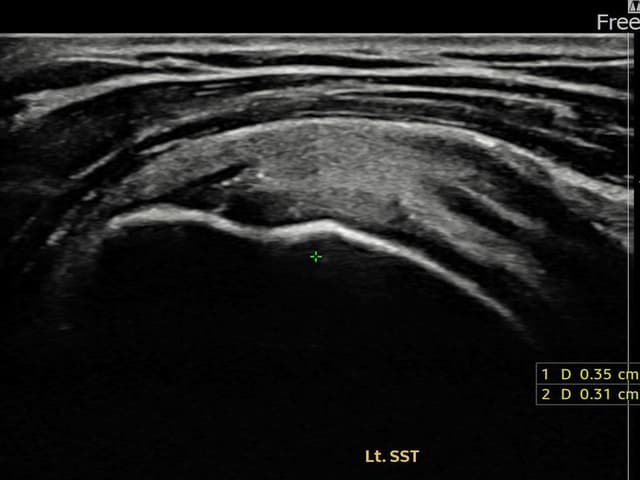

[촬영시기:22.10.06~22.11.14]

[어깨인대 축소봉합술] 좌측 어깨 극상근건 광범위 파열로 수개월간 일상생활이 어렵던 중 내원하셨습니다.